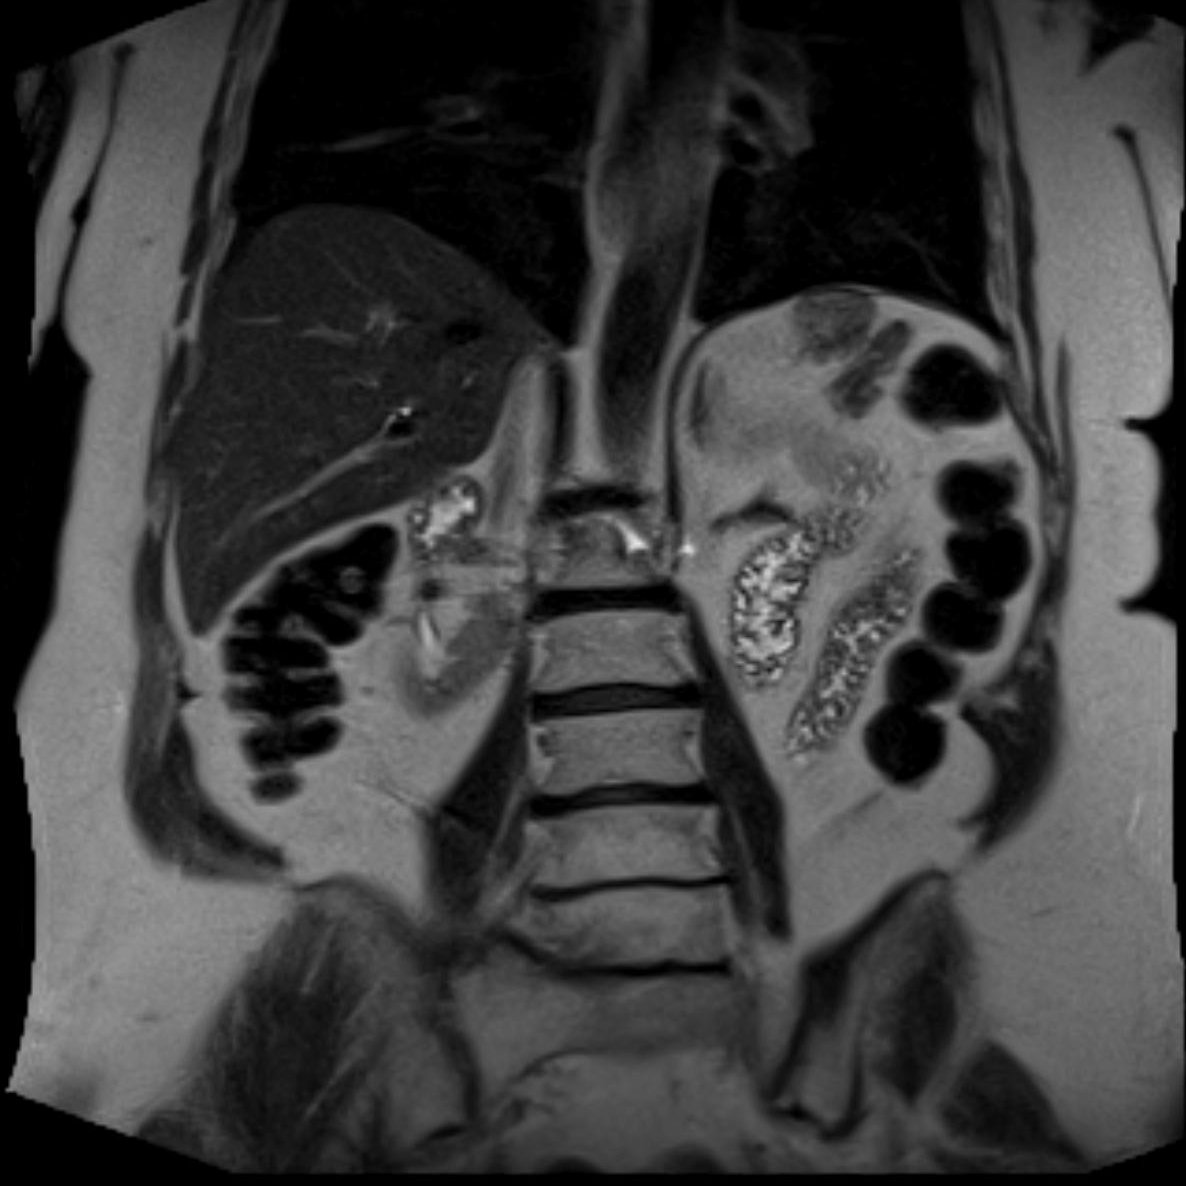

All right, all right... Where is the spleen? This patient is status post splenectomy for trauma. MRI performed 5 years later confirming benign vs indolent etiology... this is... Mesenteric SPLENOSIS! @BrighamRad @FOAMrad @SAR_RFS @futureradres @ARRS_Radiology @Abdominal_Rad